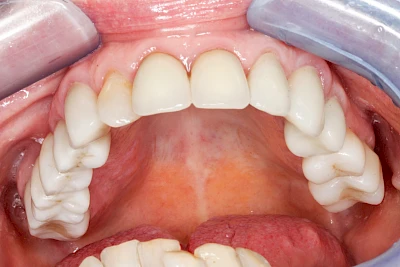

Ist zunächst nur das Zahnfleisch von der Entzündung betroffen, spricht man von Gingivitis. Später, wenn auch der Knochen um die Zähne herum entzündet ist, spricht man von einer Parodontitis. Bei der Parodontitis wird der Knochen nach und nach abgebaut und das Zahnfleisch zieht sich zurück. Die Zahnhälse und Zahnwurzeloberflächen liegen mehr und mehr frei. Die Zähne werden zunehmend lockerer und fallen schließlich aus.

Bei Implantaten – also operativ eingebrachten künstlichen Zahnwurzeln – kann der Körper die Bakterien auch nicht so gut abwehren. Hier spricht man im Fall einer Entzündung von einer Peri-Implantitis, also einer Entzündung um das Implantat herum.